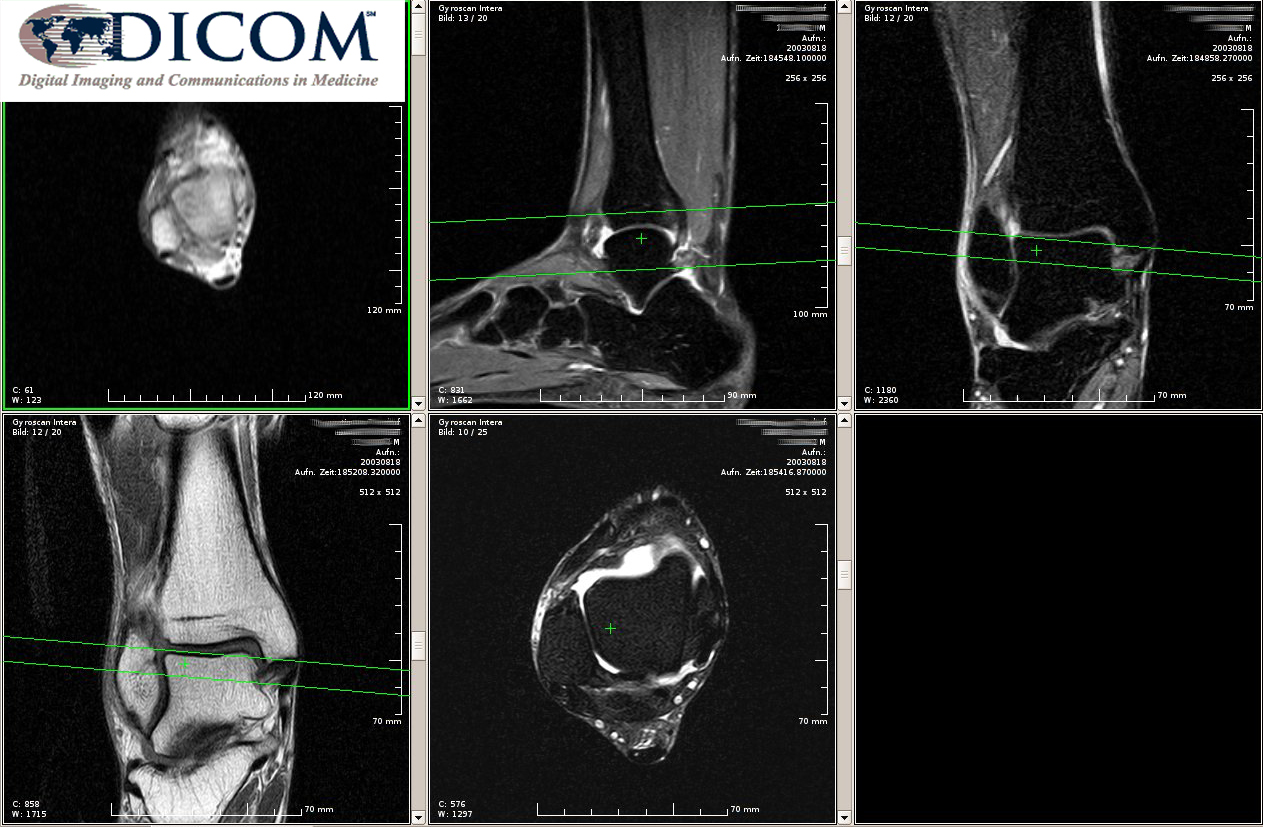

Программные решения «Первого БИТа» БИТ.Стоматология и БИТ.Управление медицинским центром получили возможность взаимодействовать с медицинским оборудованием, поддерживающим протокол DICOM. Интеграция обеспечивается с помощью дополнительного программного модуля DICOM.

• Получать от медицинской аппаратуры информацию о выполненных исследованиях в виде текстовой информации или изображений и передавать ее в медицинскую карту пациента;

Модуль DICOM поддерживает работу с медицинским оборудованием, выдающим результаты исследований в виде текста или графической информации. Поддерживается такая аппаратура, как:

• Рентгеновские аппараты;

• МРТ-сканеры;

• Аппаратура УЗИ;

• Другое оборудование, поддерживающее работу по протоколу DICOM.